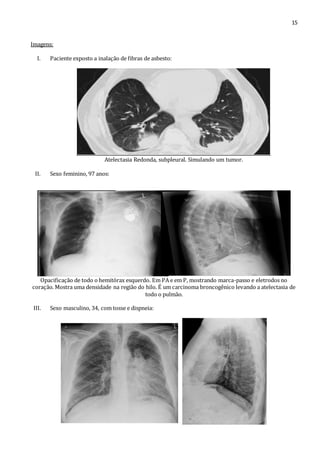

I. Paciente exposto a inalação de fibras de asbesto:

Atelectasia Redonda, subpleural. Simulando um tumor.